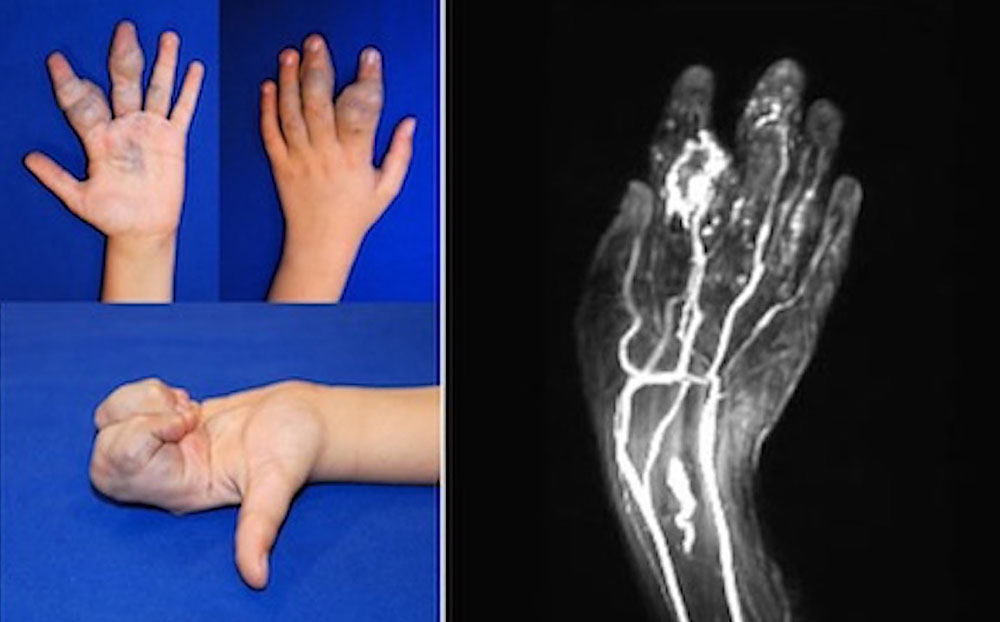

Arteriovenous malformations

Arteriovenous malformations (AVM) are characterized by continuous arteriovenous shunting in the nidus, increase in nidus size, venous dilatation and pulsations. Surgery or trauma can induce an uncontrolled increase in size. Therefore, caution should be exercised before surgical interventions. Deterioration is possible as a result of the surgery.

Arteriovenous malformations differ in the hand from venous malformations in terms of clinical signs, complaints, extent and number of fistulas. The clinical picture plays a decisive role in the decision for or against surgical therapy.

Patients with only mild symptoms, with AVM of circumscribed size, good function and low pain level should be treated conservatively.

Patients with moderately severe symptoms, with moderate AVM size and marked functional impairment and severe pain can be treated conservatively or by embolization.

Patients with pronounced symptoms, massive extension, severe ischemia, steal phenomenon with gangrene, recurrent massive bleeding, nerve compression or compartment syndrome and/or cardiac decompensation have a high surgical risk. However, severe pain and cardiac impairment are considered absolute indications for interventional or combined open operative therapy.